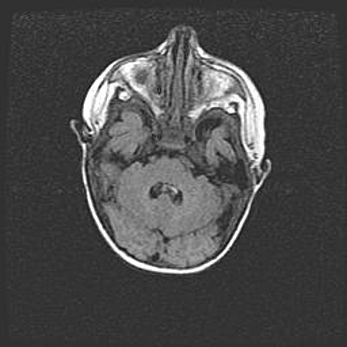

Мальформация Денди-Уокера. Киста задней черепной ямки.

Агенезия мозолистого тела.

Возраст: 2,5 месяца

Вес: 2420 г

Пол: женский

Окружность головы: 37 см

Срок гестации: 32 недели

Мальформация Денди—Уокера — редкий вид патологии ЦНС, представляющий собой врожденный порок развития каудального отдела ствола и червя мозжечка, ведущий к неполному раскрытию срединной (Мажанди) и латеральных (Лушка) апертур IV желудочка мозга. Для этогно синдрома характерна триада симптомов: гипотрофия червя мозжечка и/или полушарий мозжечка, кисты задней черепной ямки, гидроцефалия различной степени. В 70% случаев порок сочетается и с другими аномалиями головного мозга, в частности с агенезией мозолистого тела.